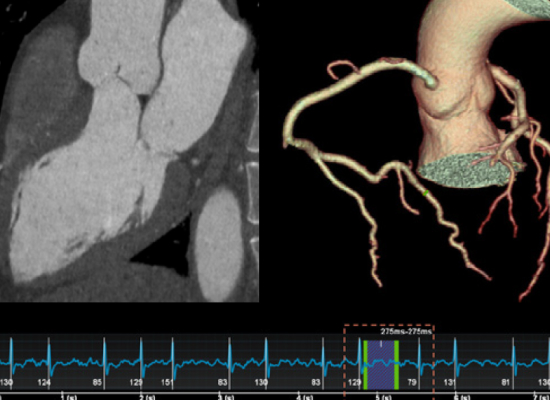

A CT Coronary Angiography (CTCA) is a specialised, non-invasive heart scan used to assess the coronary arteries—the vessels responsible for supplying blood to the heart muscle. Utilising advanced CT imaging technology, this scan produces high-resolution images that allow clinicians to detect any narrowing, blockages, or abnormalities that may indicate coronary artery disease (CAD) or other cardiovascular issues.

A member of our Quantum Radiology specialist team will arrange any required preparations, including any required dye administration, beta blockers or ECG. The patient lies comfortably on the CT scan table, which slowly moves through the scanner. The CT machine rotates around the chest, capturing a series of high-resolution images. These are reconstructed into a detailed view of the heart and coronary vessels.